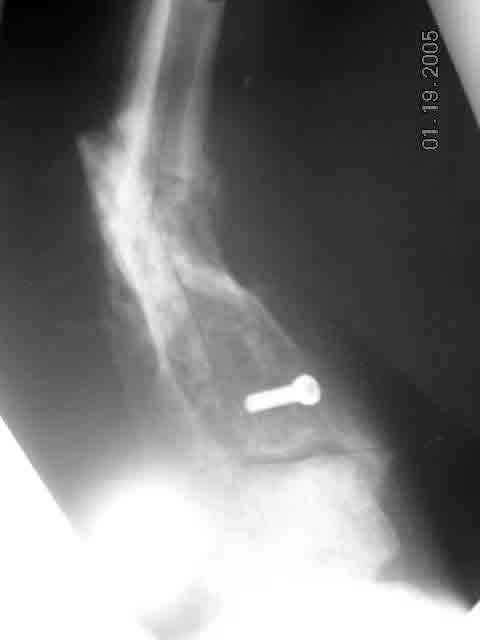

mal-non-union distal tibia in a diabetic |

Dear Group,Would like to present following case.68 yr old diabetic patient who sustained fractured distal tibia and fibula in distal third, treated with intramedullary rod. 4 weeks later, screws broke, sending tibial nail through distal tibia. Nail removed and external fixator applied. At time of ex-fix, blood supplyto foot noted to be nil. (Oxygen saturatioon of great toe 0%). Patient then underwent arterial bypass surgery which has restored blood supply. Ex-fix removed at 5 months with what appeared to be healing. Patient was then allowed to walk on the leg. He returns one month after weight bearing allowed with accomnpanying x-rays. My plan was to open non-union site, curette out fibrous tissue, bone graft and apply ex-fix (Ilizarov Type). Question: Would anyone opt for a repeat im nailing after opening and curretage and bone grafting?Thanks in advance,Louis D. Nunez, MDFishkill, NY

Why not closed nailing only, without any site opening? I would use 12 mm (so minimal reaming) closed section titanium nail with all locking options in the distal fragment, statically locked for 2-3 month. If site mobility now is not loose, it makes sense to apply ex-fix for gradual alignment before. PerQ osteotomy of the fibula if needed (presented x-rays don't show whether it is healed). The nail becomes shaft endoprosthesis so the leg immediately must be fully loadable regardless bony union.